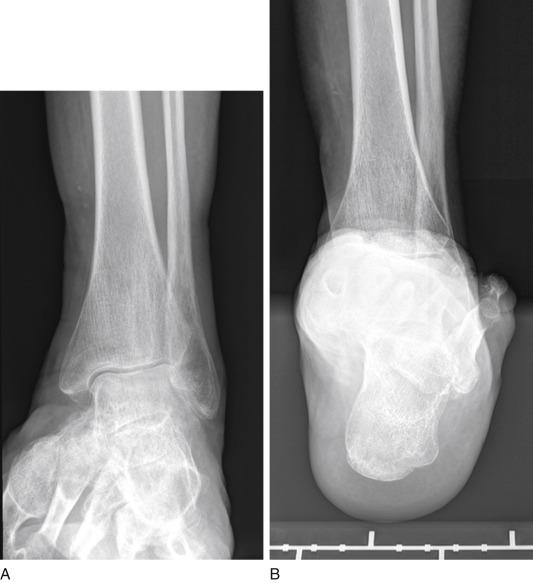

• Advanced stage of Mueller-Weiss syndrome ( Fig. 25.1 ) with

FIG. 25.1